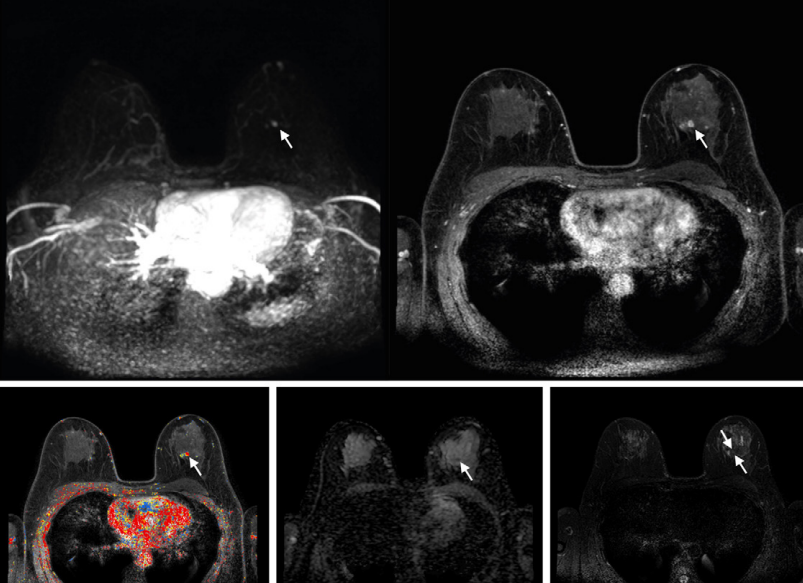

McCarthy and co-authors analyzed the potential differences in eligibility for the Pennsylvania supplemental screening criteria based on breast density between Black and white women. Their cross-sectional study included 68,478 Black and white women, aged 40 to 74 years, who did not have prior breast cancer or known BRCA1/2 variants. The women underwent mammography screening from 2015 to 2021. The team used the Breast Cancer Risk Assessment Tool (BCRAT) to measure lifetime risk.

The team reported that fewer Black women had extremely dense breasts and higher lifetime risk compared with white women. Consequently, this led to less Black women meeting the eligibility criteria for insurance coverage.